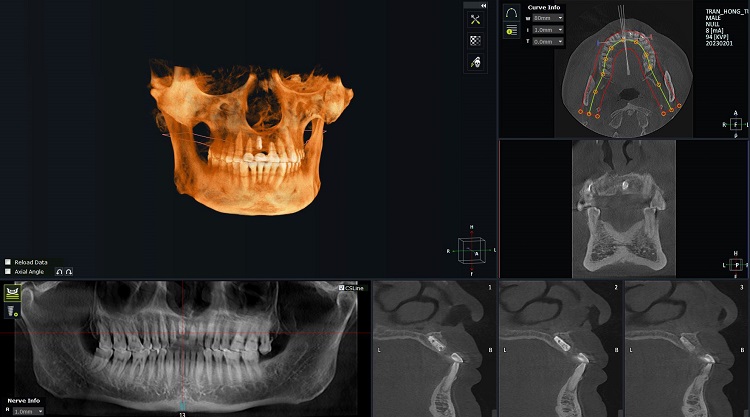

Qua kiểm tra, thăm khám, chụp phim CT Conebeam và dựa trên các dữ liệu ban đầu, bác sĩ tại Nha khoa Lạc Việt đã lên kế hoạch điều trị cụ thể như sau:

Hình ảnh phim chụp sau cấy ghép implant của chú Tuyến (Ảnh: Nha khoa Lạc Việt Intech)